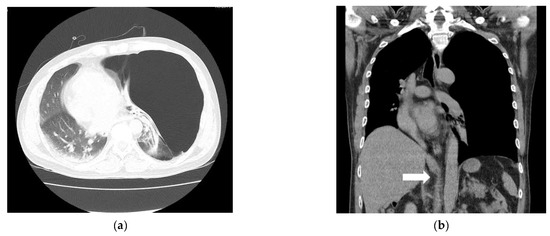

For the diagnosis of a GEB, a chest X-ray is primarily performed. X-ray findings have shown large bullae that account for one-third of the hemithorax, lung parenchyma atelectasis, inverted ipsilateral diaphragm, and contralateral displacement of the mediastinum [8]. GEBs and pneumothorax are different in chest X-rays. In the chest CT scan, there was no pneumothorax, but giant bullae were shown over the entire lung. In the case of a GEB, the entire parenchyma is compressed downward in the direction of the costal angle, while a pneumothorax appears as a lung parenchyma that collapses into a clump toward the hilum [9]. However, plain chest X-rays and physical examinations cannot provide accurate anatomical information on the findings. In addition, if a CTD is mistakenly inserted for a pneumothorax, the GEB, which has a very thin wall compared to the normal lung parenchyma, is easily damaged and can lead to a dangerous situation, such as tension pneumothorax. Therefore, chest CT is more appropriate as a test for differentiating GEBs [10]. CT can also be a good test, as it can diagnose other coexisting diseases. In the present case, the left lung was radiolucent on chest PA, and the mediastinum was deviated to the right, suggesting tension pneumothorax (Figure 1a). In the chest CT scans, it was revealed that it was not a pneumothorax, as giant bullae were shown over the entire lung. These giant bullae caused a mass effect that deviated the mediastinum (Figure 2a). In addition, it could be seen that the inferior vena cava (IVC) was bent due to the mediastinal shift in the coronal plane of the chest CT (Figure 2b). This can lead to cardiovascular collapse due to the mass effect of the GEB itself, as well as tension pneumothorax due to the rupturing of the GEB. We speculate that this mass effect might have been exaggerated by muscle relaxation after succinylcholine use. Superior vena cava syndrome caused by a GEB pressing the superior vena cava has been reported [11]. However, cases showing IVC-syndrome-like symptoms by pressing the IVC have not yet been reported.

Figure 2. Giant bullae caused a mass effect that deviated the mediastinum (a). The inferior vena cava (IVC) was bent due to the mediastinal shift (white arrow) (b).